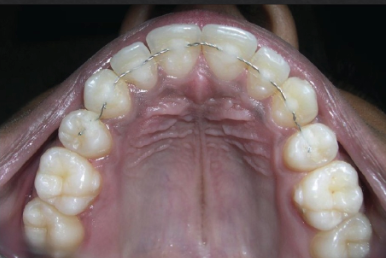

what’s splinting

mechanical stabilization of teeth

when is splinting indicated

for pt comfort on mobile teeth

pathologic tooth migration

guided tissue regeneration on mobile teeth

prosthetics where multiple abutments needed